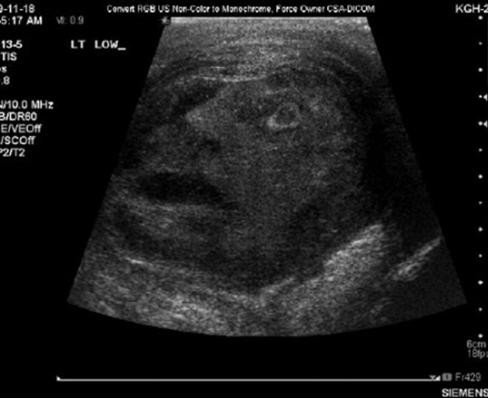

암세포 악마의 얼굴, "암치료 받는 환자 얼굴 같아.."

일명 '암세포 악마의 얼굴'이 발견돼 화제가 되고 있다.최근 한 온라인 커뮤니티 게시판에 '몸속에서 악마의 얼굴 포착'이라는 글과 함께 초음파 사진이 게재됐다.공개된 사진은 지난달...

2011.11.07 뉴데일리 > 글로벌 > 진보라